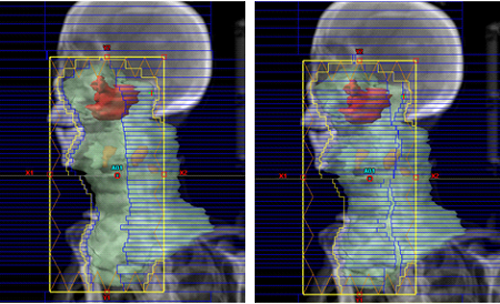

図 中咽頭癌に対するIMRTの線量分布

頭頚部腫瘍には、脳、視神経、脊髄、眼球、耳下腺などの重要な正常臓器が近接しており、治療においてはこれらの臓器への影響を最小限に抑えることが求められます。

当院では、頭頚部癌に対する放射線治療をVMAT(強度変調回転放射線治療)で実施しています。

VMATを用いることで、腫瘍に対する十分な線量を確保しつつ、正常組織の線量を最小限に抑えることが可能です。

照射回数は30~35回(総線量60~70グレイ)で、1日1回、週5回のスケジュールです。